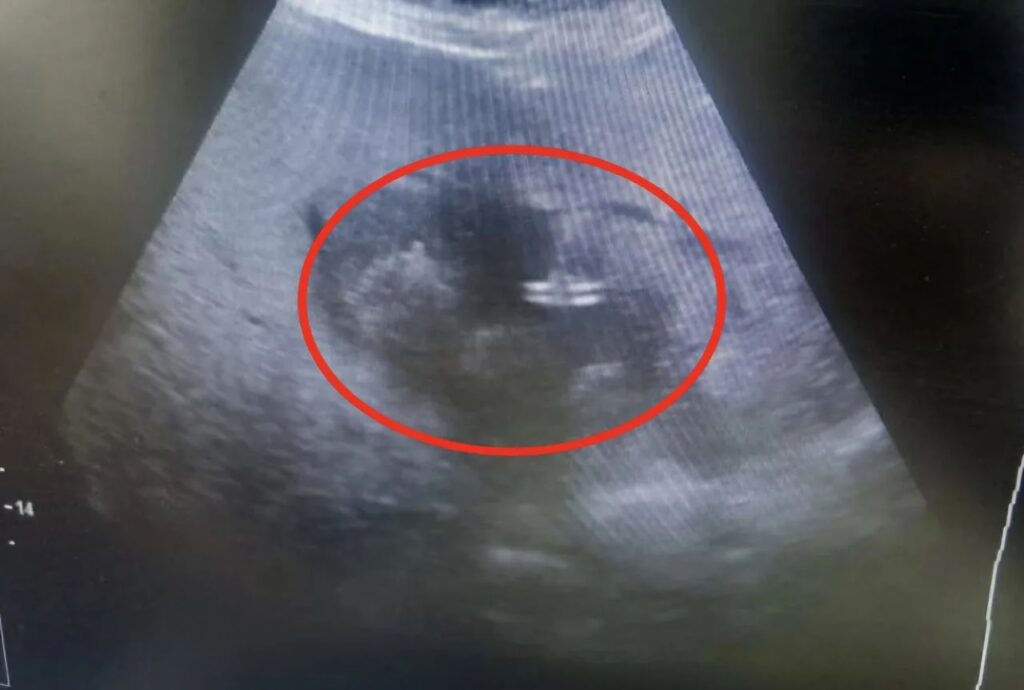

Балаковские врачи спасли 83-летнюю пациентку. В гнойное хирургическое отделение Балаковской городской клинической больницы поступила 83-летняя женщина, переведенная из нефрологии. Две недели высокой температуры и недомогания завершились серьезным диагнозом — обширный абсцесс печени размером около 10 сантиметров.

Возраст пациентки и сопутствующие риски делали традиционную полостную операцию опасной. Однако балаковские врачи нашли альтернативу. Благодаря междисциплинарному подходу и современным технологиям, хирурги выполнили малоинвазивное дренирование абсцесса под контролем ультразвуковой навигации.

Методика позволяет с ювелирной точностью ввести дренаж прямо в полость гнойника, практически не травмируя окружающие ткани. Для пожилых пациентов это особенно важно — восстановление проходит быстрее, а риски кровопотери и осложнений сведены к минимуму.

Как отметила Ирина Власова, задача врачей ультразвуковой диагностики — обеспечить попадание дренажа строго в целевую зону, исключив повреждение окружающих тканей. Именно такой подход позволяет пожилым пациентам восстанавливаться быстро и без последствий.